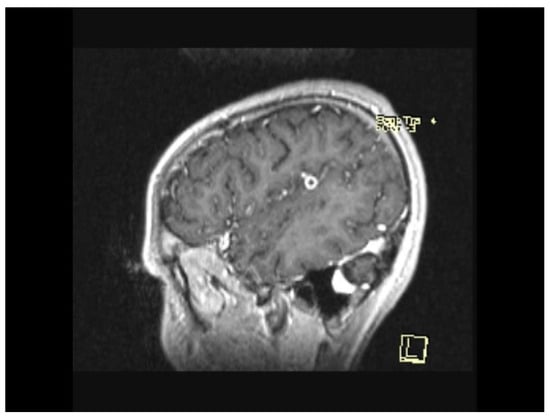

2. Case Presentation